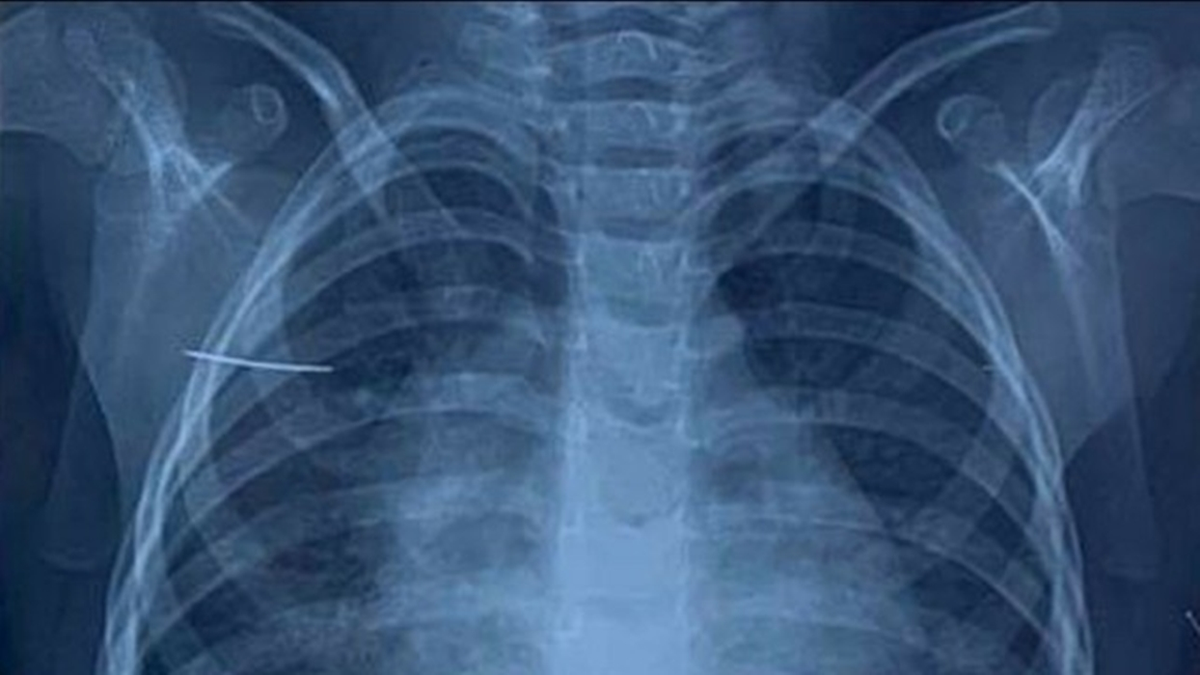

Trên phim chụp X-quang của bệnh nhi. (Ảnh:BVCC)

Tại Bệnh viện Nhi Trung ương, khi tiến hành cho bệnh nhi chụp X-quang và cắt vi tính lồng ngực, các bác sĩ phát hiện dị vật hình kim khâu nằm tại vị trí mặt trước xương bả vai. Cháu C được chỉ định phẫu thuật để lấy vị vật ra khỏi cơ thể.

Bác sĩ Nguyễn Minh Khôi, khoa Ngoại tổng hợp, người trực tiếp phẫu thuật cho bé C chia sẻ: “Trong quá trình phẫu thuật nội soi bằng 03 trocar đi vào tổ chức giữa cơ dưới vai và cơ thang, các bác sĩ phát hiện dị vật nằm lẫn trong các sợi cơ là chiếc kim khâu dài 3.8cm, đầu nhọn. Sau 1giờ, dị vật đã được lấy ra hoàn toàn, không đứt gãy”.

Trong trường hợp của cháu C, dị vật được các bác sĩ xác định chính xác nhờ phim chụp cắt lớp 128 dãy có dựng hình kết hợp phẫu thuật nội soi vào khoang dưới cân nông giúp giảm sang chấn, tổn thương tổ chức và thẩm mỹ sau mổ.